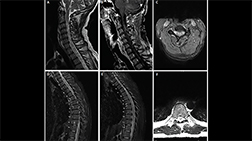

A. Brain MRI from Mr. L’s initial hospitalization with increased signal intensity in the right temporal lobe

B. Brain MRI with enhancement of the temporal lesion (small arrow) with leptomeningeal enhancement (large arrow).

Brain MRI from Mr. L’s second hospitalization demonstrates resolution of the previously visualized right temporal lesion and leptomeningeal enhancement.